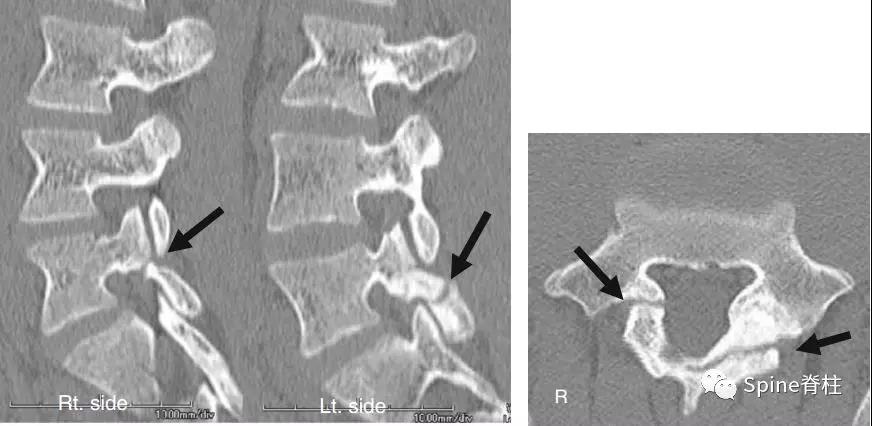

图:L5半椎板裂15岁篮球运动员,严重腰痛,影响睡眠CT示:左侧为椎板裂(箭头),右侧为峡部裂(箭头)